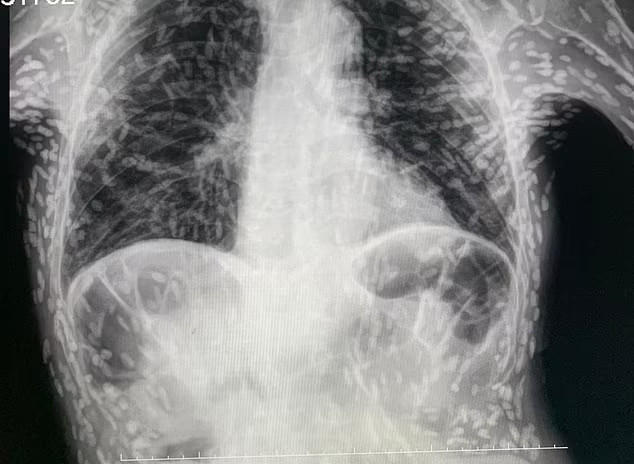

13/05/2023 06:21Phim X-quang hé lộ nguyên nhân ít ngờ khiến bệnh nhân ho dai dẳng

Theo Daily Mail, hình ảnh do bác sĩ Vitor Borin de Souza (Bệnh viện Clinicas in Botucatu, Brazil) cung cấp. Trên phim có hàng trăm đốm trắng, mỗi đốm đại diện cho phần bị vôi hóa của một loại ký sinh trùng.

Tình trạng này, được gọi là bệnh nang sán, xảy ra khi ấu trùng của một loài sán dây, thường sống trong ruột, xâm nhập vào các mô như cơ hoặc não. Ở đó, chúng tạo thành các nốt cứng giống như u nang dưới da.

Mặc dù gây khó chịu nhưng các ấu trùng đã chết nên thường vô hại trừ khi tồn tại trong não, dây thần kinh hoặc mắt. Bác sĩ Souza lý giải: “Người bệnh ăn phải trứng sán dây (tồn tại trong chất thải của người bị sán dây). Bởi vậy, bạn phải rửa kỹ thực phẩm trước khi ăn”.

Bệnh nhân trên cần chụp MRI để kiểm tra có bất kỳ u nang nào trong não hay không. Nếu tồn tại ở vị trí đó, các u nang do ký sinh trùng để lại có thể gây ra nguy hại cho sức khỏe.

Khi đó, bệnh nhân có thể đau đầu, thậm chí co giật, lú lẫn, chóng mặt và não úng thủy, tình trạng dư thừa chất lỏng trong não. Bác sĩ thường chỉ định loại bỏ u nang trong những trường hợp này. U nang cũng có thể xâm nhập vào mắt, gây mờ hoặc rối loạn thị lực và có khả năng gây nhiễm trùng.

Bản thân các u nang có thể chỉ phát triển vài tháng hoặc vài năm sau khi nhiễm trứng sán dây ban đầu.

Sán dây gây bệnh nang sán có tên là Taenia solium, còn được gọi là sán dây lợn. Trứng của loài này được truyền từ người sang người qua phân, do nguồn nước bị nhiễm bệnh hoặc rửa tay không sạch sẽ khi chuẩn bị thức ăn.

Tổ chức Y tế Thế giới (WHO) ước tính ấu trùng Taenia solium phát triển trong não là nguyên nhân gây ra tới 70% các trường hợp động kinh ở một số nơi trên thế giới. Khoảng 2,5 triệu người được cho là nhiễm Taenia solium mỗi năm, phổ biến ở các vùng nghèo của châu Á, Nam Mỹ và Đông Âu.